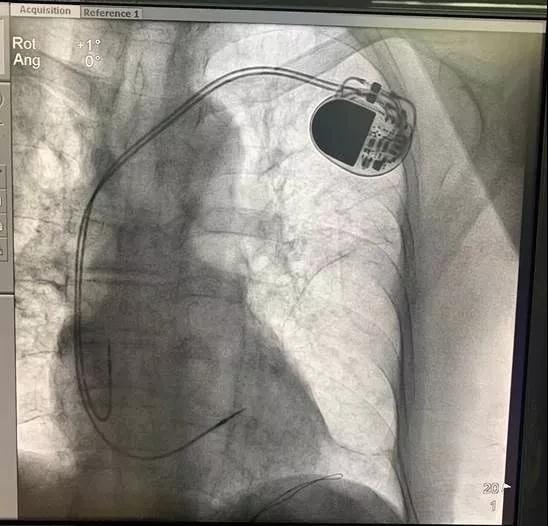

近日,浙江大学医学院附属第二医院(简称浙大二院)心内科在浙江省公立医院中首次顺利地为一位病窦的病人植入了新型国产自动化芯彤心脏起搏器。

该患者为83岁高龄男性,头晕2月余,入院后24小时动态心电图提示“窦性心律,房早26237个,227次停搏,最长达4.44秒”。查体一般情况尚可,精神可,无心力衰竭症状与体征,拟行起搏器植入术。经过仔细术前评估,详细解释起搏器植入的必要性、相关风险及术后注意事项,在病人及家属知情同意后,浙大二院心内科项美香教授团队顺利地为该病人植入了新型国产自动化芯彤心脏起搏器。

此次为病人植入的芯彤心脏起搏器,是基于美敦力公司先进的起搏器技术和严格的质量标准由深圳先健科技生产的国产起搏器,拥有1.3Ah大容量电池,心房心室自动阈值管理等多项自动化技术,配套有主动和被动电极,并由美敦力公司提供技术支持与服务,医生和患者在使用国产起搏器的同时,可享受到进口产品的服务。